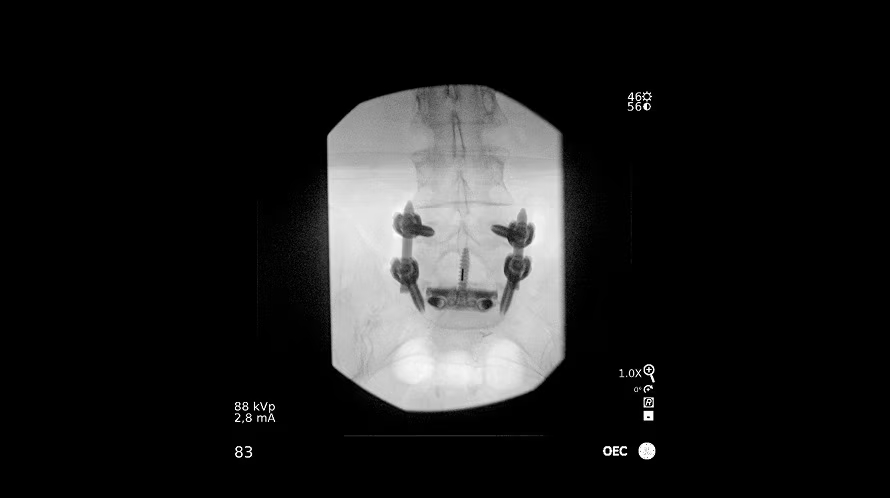

GE OEC Elite CFD относится к мобильным рентгенохирургическим системам премиум-уровня и предназначена для проведения интраоперационных рентгеноскопических и рентгенографических исследований в хирургии, травматологии, ортопедии, сосудистых и эндоваскулярных вмешательствах, нейрохирургии и урологии. Плоскопанельный КМОП-детектор с полем обзора 21×21 см, высоким динамическим диапазоном и частотой до 30 кадров/с обеспечивает детализированную визуализацию костных структур, мягких тканей и контрастированных сосудов в режиме реального времени. Передача изображения 1:1 на 32-дюймовый 4K-монитор просмотровой станции позволяет хирургу уверенно ориентироваться в операционном поле, контролировать положение инструментов и имплантов, минимизируя количество повторных экспозиций.

- Интеллектуальные профили обработки: общая хирургия, ортопедия, спинальная хирургия, контрастные исследования, ангиография, кардиография.